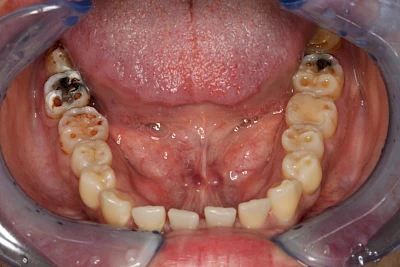

Über die Zeit können verschiedene Prozesse die Zahnhartsubstanzen aufzehren:

- Abnutzung durch Kauen (Abrasion) oder duch durch übermäßiges Knirschen bzw. Pressen (Attrition)

- Säurebedingte Auswaschung (Erosion)

Auswaschung (Erosion) dagegen ist eine Verschleißerscheinung der Zähne aufgrund von immer wiederkehrenden Säureangriffen durch die Nahrung, verstärkt zum Beispiel durch den Genuss säurehaltiger Getränke oder Speisen. Auch bei Menschen mit einer Essstörung (z. B. Bulimie) können die Zähne durch die Magensäure ausgewaschen erscheinen.